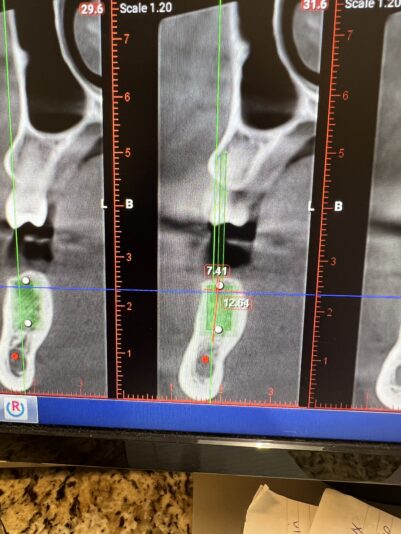

Dustin started the discussion Single implant tx planning in the forum Implant Tx Planning 2 years ago

Hi everyone. I am new to placing implants and have been planning some cases and a couple have made me question what the proper plan should be.

Case #1 patient has limited mesiodistal space. Nearing 6mm. It is #5 location. My main concern is obviously lack on space but also what size implant is appropriate for certain teeth. This area has…